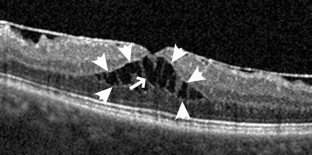

Abb. 3